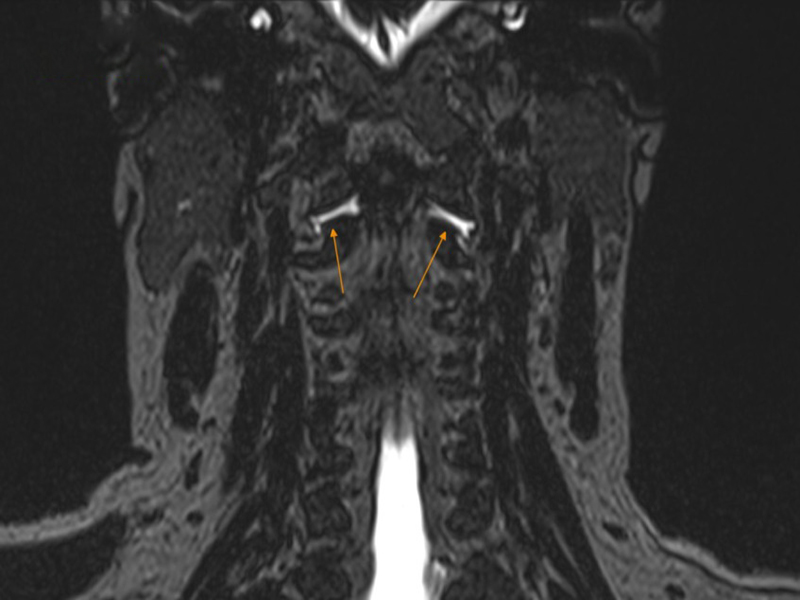

Kết quả chụp cắt lớp vi tính myelography tại bệnh viện Tâm Anh cho thấy chị bị rò dịch não tủy, hai điểm rò ở vị trí đốt sống cổ số một và số hai, sát xương chẩm. Dịch rò ra có hai loại là rò ra ngoài da hay rò dưới da. Rò ra ngoài da gặp ở rò thứ phát, có thể thấy được dịch não tủy bằng xét nghiệm; còn rò dưới da gặp trong rò tự phát, dịch thấm lại vào trong cơ thể nên rất khó phát hiện.

Phó giáo sư Hiền khuyên người bệnh khi có các triệu chứng này cần đi khám ngay ở cơ sở y tế có chuyên khoa thần kinh và đầy đủ thiết bị chẩn đoán hình ảnh hiện đại. Chẩn đoán rò dịch não tủy bằng cách chụp cộng hưởng từ, kết hợp chụp cắt lớp vi tính có bơm thuốc cản quang để xác định vị trí rò và loại rò, từ đó can thiệp phù hợp.